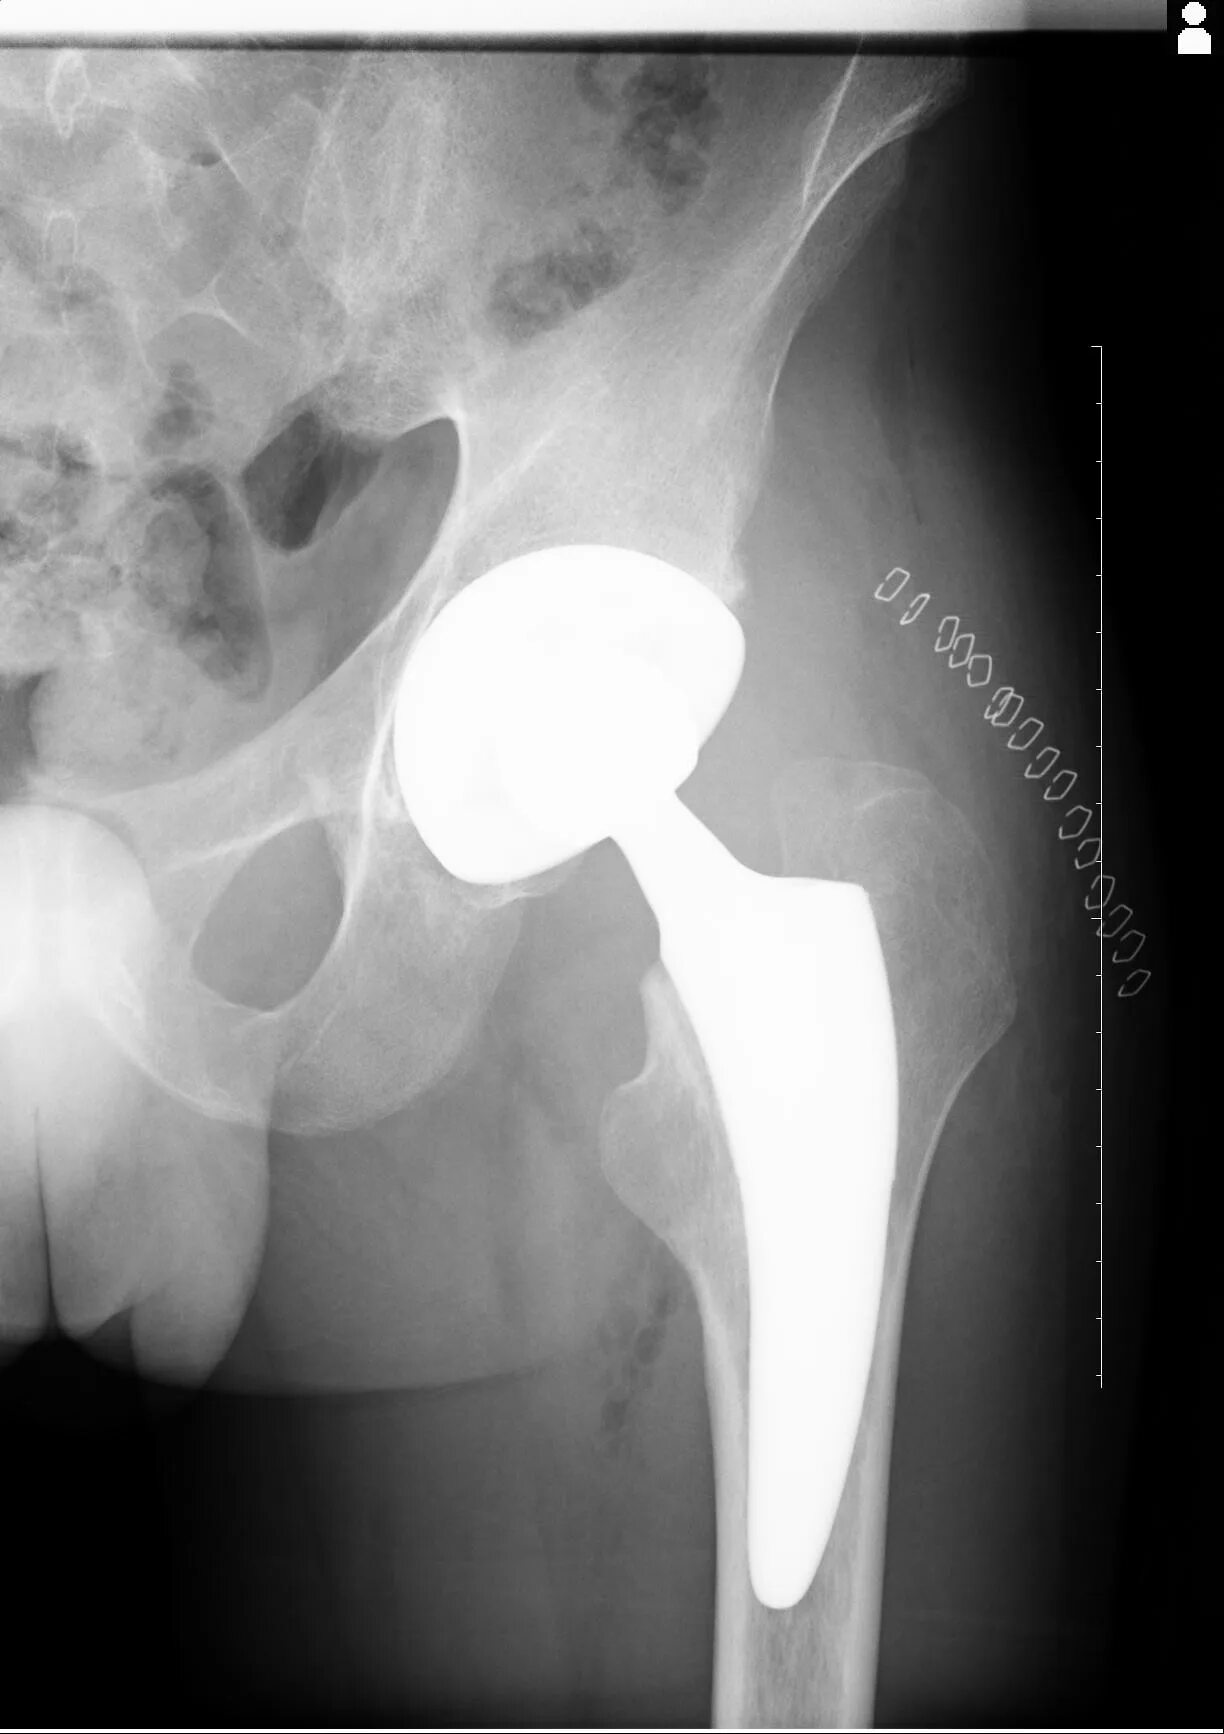

Протезы тазобедренных суставов по квоте